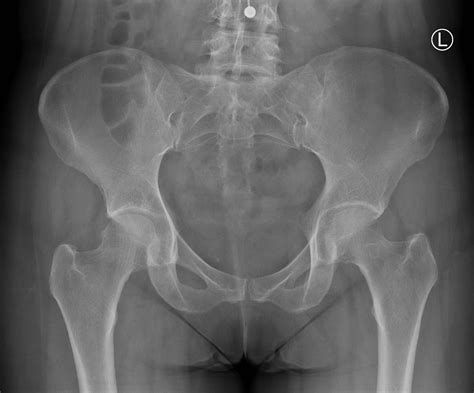

Normal Hip X Rays are a type of radiographic imaging used to visualize the hip joint and surrounding structures. This non-invasive procedure helps diagnose a wide range of conditions, including fractures, dislocations, arthritis, and developmental issues. The hip joint is a complex structure composed of the femoral head, acetabulum, and supporting ligaments and muscles. Normal Hip X Rays provide a clear view of these components, aiding in accurate diagnosis and treatment planning.

• Imaging: The radiographer positions the X-ray machine over the hip area and takes multiple images from different angles. These views typically include an anteroposterior (AP) view, which shows the front of the hip, and a lateral view, which shows the side of the hip.

Interpreting Normal Hip X Rays requires a trained eye and a thorough understanding of hip anatomy. Radiologists look for specific features and measurements to determine the health of the hip joint. Key areas of focus include:

• Bone Density: Normal bone density indicates healthy bone structure. Any areas of decreased density may suggest osteoporosis or other bone diseases.

• Joint Space: The space between the femoral head and the acetabulum should be uniform and well-defined. Narrowing of this space can indicate arthritis or other degenerative conditions.

• Alignment: Proper alignment of the femoral head within the acetabulum is crucial. Misalignment can suggest dislocations, fractures, or developmental issues.